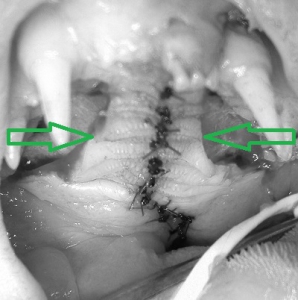

下の写真が手術後のものです。口と鼻をつなぐ穴が非常に大きいため、通常の方法では縫合することができません。このために左右の口蓋粘膜をはがして中央に移動させて縫合しています。時間はかかりましたが、これで完了です。